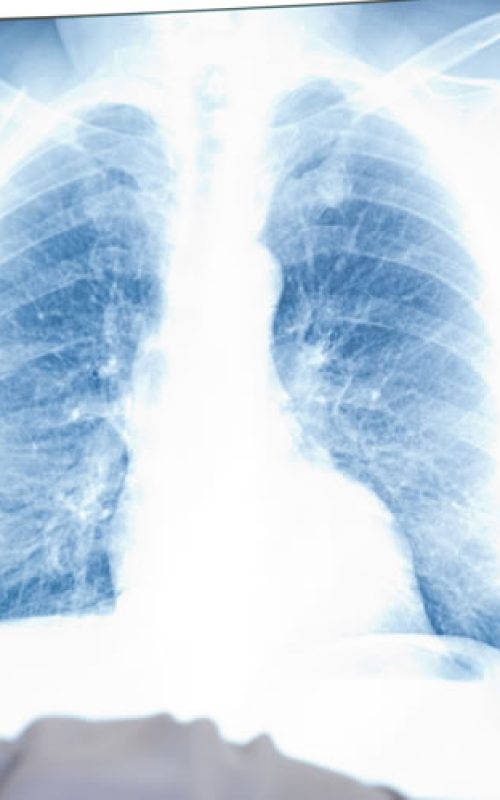

Câncer de Pulmão

O câncer de pulmão pode começar nas células que revestem os brônquios e partes do pulmão, como os bronquíolos e alvéolos.

O câncer de pulmão se desenvolve a partir do crescimento desordenado das células provocando o aparecimento de um tumor. Esse tumor tem a capacidade de se disseminar para outras partes do corpo.

Os diferentes tipos de câncer de pulmão podem aparecer também em diferentes tipos de células que pertencem ao órgão, por exemplo, células dos brônquios, dos bronquíolos ou dos alvéolos.